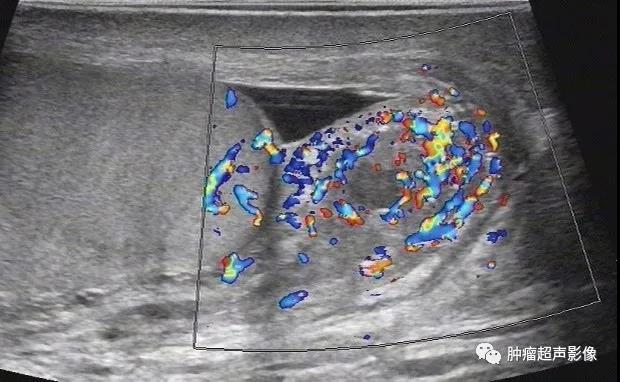

急性附睾炎:左侧附睾整个弥漫性不均质肿大,血流稍丰富。